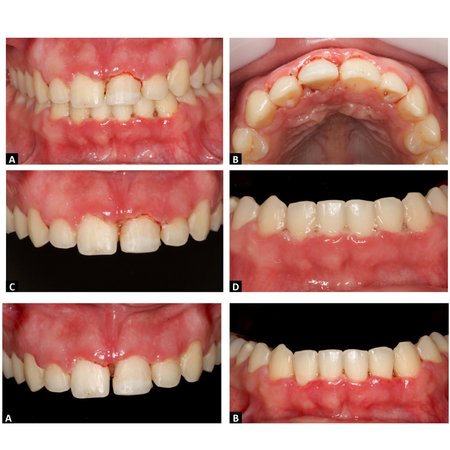

OBJETIVO: O objetivo do presente estudo foi descrever a conduta terapêutica inicial e de manutenção de uma paciente com um quadro clínico de gengivite necrosante. RELATO DE CASO: Paciente leucoderma, sexo feminino, 20 anos de idade, sem problemas sistêmicos, revelou queixa de dor e sangramento gengival à escovação. Ao exame clínico, verificou-se acúmulo de biofilme em todas as faces dentárias, com papilas interdentais e margem gengival recobertas por epitélio necrótico com...

OBJECTIVE: To describe the initial and maintenance treatments of a patient with clinical manifestation of necrotizing gingivitis. CASE REPORT: A 20-year-old Caucasoid female patient, without systemic problems, complained of pain and gingival bleeding upon brushing. Clinical examination revealed biofilm accumulation on all tooth surfaces, with interdental papillae and gingival margins covered by necrotic epithelium with hemorrhagic areas and intense inflammatory process in both arches....